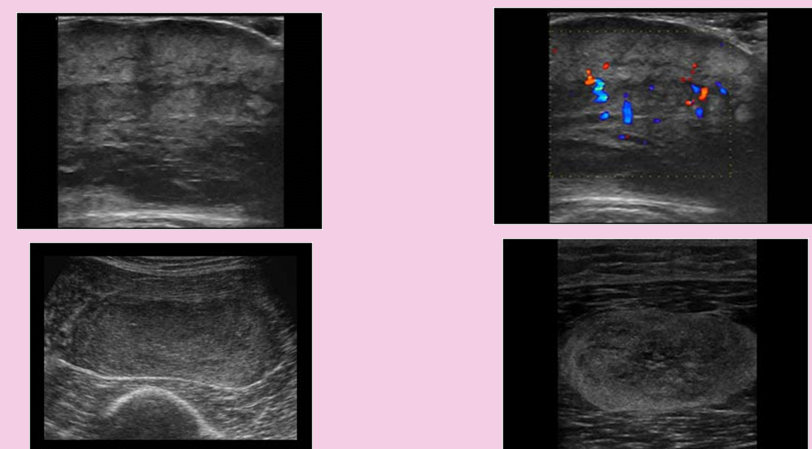

what is this?

soft tissue masses

benign

lipoma (most common)

firboma

leiomyoma

pseudoaneurysm